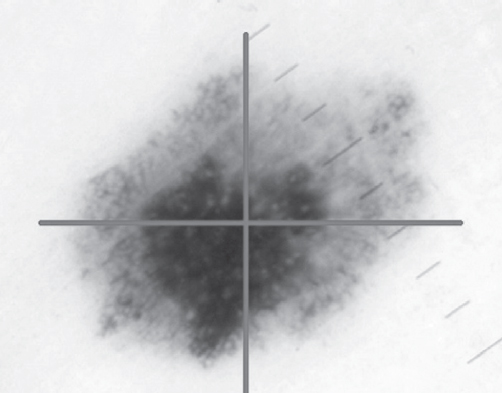

Анализ частоты встречаемости десяти признаков меланоцитарных новообразований при проведении дерматоскопии 34 гистологически верифицированных новообразований кожи (11 меланом и 23 меланоцитарных невуса) показал, что признак «асимметрия пигментации и строения» (рис. 1) присутствовал в меланомах в 11 случаях, в невусах — в 8 случаях. Признак «атипичные глобулы» присутствовал в меланомах в 7 случаях, в невусах — в 9 случаях. Признак «асимметричные полосы» присутствовал в меланомах в 6 случаях, в невусах — в 8 случаях. Признак «атипичная пигментная сеть» (рис. 2) присутствовал в меланомах в 8 случаях, в невусах — в 17 случаях. Признак «бело-голубая вуаль» присутствовал в меланомах в 10 случаях, в невусах — в 4 случаях. Признак «асимметричные зоны гиперпигментации» (рис. 3) присутствовал в меланомах в 11 случаях, в невусах — в 18 случаях. Признак «зернистость» присутствовал в меланомах в 4 случаях, в невусах — в 1 случае. Признак «рубцовоподобные очаги гипопигментации» (рис. 4) присутствовал в меланомах в 4 случаях, в невусах — в 2 случаях. Признак «белые блестящие полосы» присутствовал в меланомах в 5 случаях, в невусах не встречался. Признак «негативная пигментная сеть» присутствовал в меланомах в 1 случае, в невусах — в 2 случаях.

Рис. 1. Асимметрия пигментации и строения

Оценивая полученные результаты можно констатировать, что наибольшую ДЧ имели следующие признаки: асимметрия пигментации и строения (100 %), асимметричные зоны гиперпигментации (100 %) и бело-голубая вуаль (90,9 %). Наибольшую ДС имели следующие признаки: белые блестящие полосы (100 %), зернистость (95,6 %) и рубцовоподобные очаги депигментации (91,3 %). Наибольшую ДЭ имели следующие признаки: бело-голубая вуаль (86,8 %), асимметрия пигментации и строения (82,6 %) и белые блестящие полосы (72,8 %).